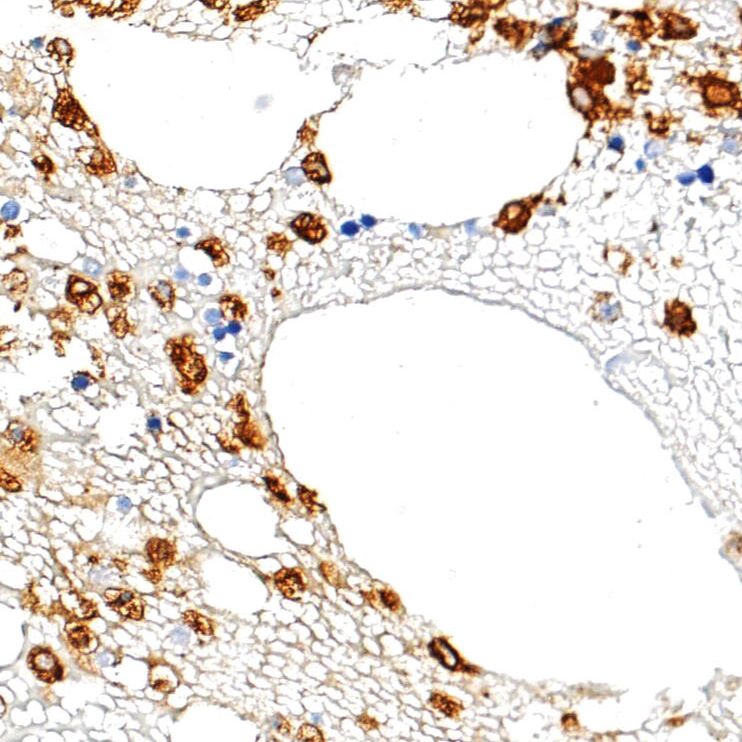

中杉金桥 ZA-0197 Myeloperoxidase 抗体试剂 (免疫组织化学),产品简介:

产品名称:Myeloperoxidase 抗体试剂 (免疫组织化学)

应用: Myeloperoxidase(MPO)基因位于17号染色体,与人甲状腺过氧化物酶具有同源性。髓过氧化物酶抗体是骨髓细胞的特异性标记。在外周血涂片中,粒细胞呈强阳性反应,单核细胞呈弱阳性反应,而其它细胞不反应;在骨髓涂片中,用于标记粒系细胞。MPO在急性骨髓性白血病、粒细胞性白血病、单核细胞性白血病、成髓细胞瘤和其它造血系统疾病的成髓细胞和未成熟骨髓细胞中表达。在某些肺癌和卵巢癌也可见表达。用于淋巴造血系统疾病的研究

阳性部位: 细胞质

阳性对照: 骨髓穿刺组织